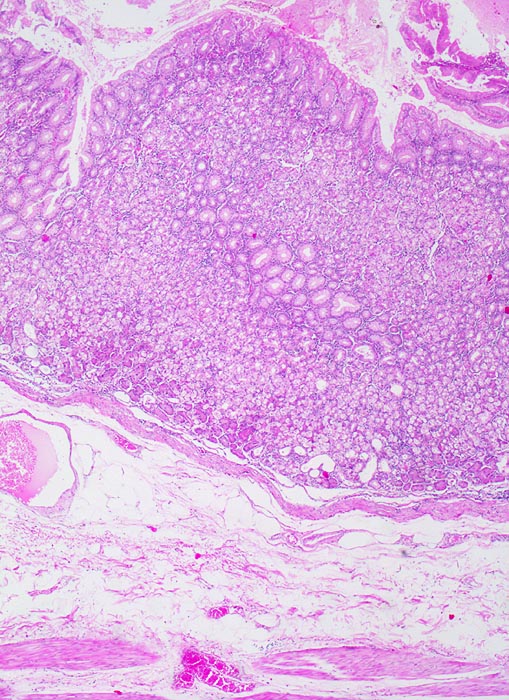

Die ersten beiden Typen entsprechen histologisch meist einem intestinalen Typ nach Lauren (> 1342). Diese Tumoren sind scharf begrenzt, bilden tubuläre oder papilläre Strukturen wie die Dickdarmkarzinome, sind meist assoziiert mit bekannten umweltbedingten Risikofaktoren und haben eine bessere Prognose.

• Gewebsfragment aus gastroösophagealem Übergang.

• Das unscharf begrenzte Karzinom breitet sich diffus in der gesamten Magenwand und in der Ösophaguswand aus bis in des periösophageale und subseröse Fettgewebe.

• Ösophagus mit intaktem plattenepithelialem Schleimhautüberzug.